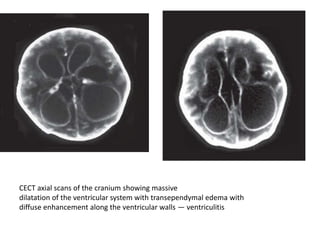

CECT axial scans of the cranium showing massive

dilatation of the ventricular system with transependymal edema with

diffuse enhancement along the ventricular walls — ventriculitis